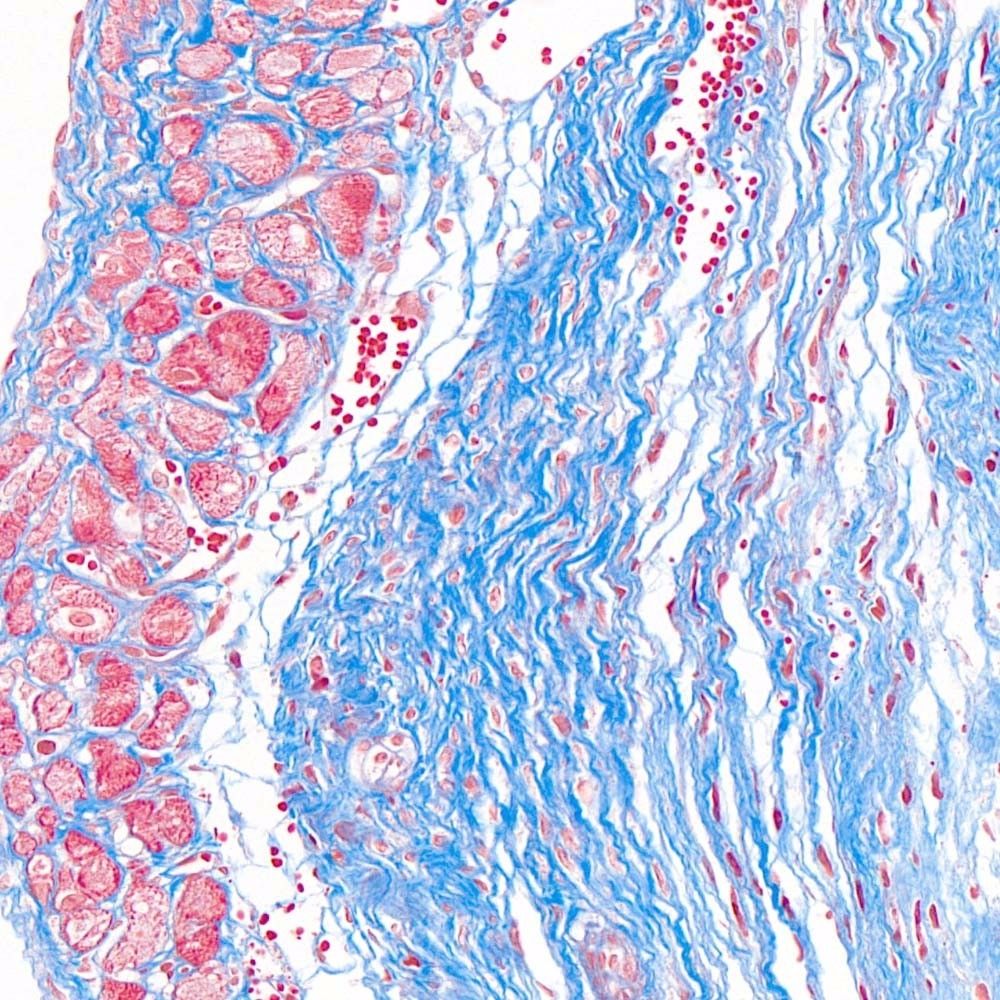

MASSON(馬松)染色實(shí)驗(yàn)過(guò)程中常見(jiàn)問(wèn)題和解決方法由普拉特澤生物技術(shù)為大家總結(jié)分享。本文是關(guān)于MASSON染色實(shí)驗(yàn)的最后一篇介紹,前面我們深入了解了MASSON染色:原理、步驟與實(shí)例、如何進(jìn)行MASSON染色?、MASSON染色方法及其在實(shí)驗(yàn)室的應(yīng)用可以點(diǎn)擊標(biāo)題直接傳送回去學(xué)習(xí)的哦。普拉特澤生物病理檢測(cè)平臺(tái)承接MASSON實(shí)驗(yàn)外包上百例,早就為大家把實(shí)驗(yàn)過(guò)程中要踩的雷、吃的虧幫大家吃完了,現(xiàn)在我們就來(lái)看看,實(shí)驗(yàn)過(guò)程中還有哪些常見(jiàn)的問(wèn)題和解決方法吧!

除了以上常見(jiàn)問(wèn)題外,實(shí)驗(yàn)者在操作過(guò)程中還應(yīng)注意以下幾點(diǎn):首先,蘇木素用于細(xì)胞核的染色,染色時(shí)間可根據(jù)實(shí)際情況自行調(diào)整;其次,MASSON復(fù)合染色液經(jīng)磷鉬酸分化時(shí)須用顯微鏡控制,確保肌纖維和膠原纖維呈現(xiàn)正確的顏色;最后,組織固定是實(shí)驗(yàn)成功的關(guān)鍵,應(yīng)選擇合適的固定劑并控制固定時(shí)間。